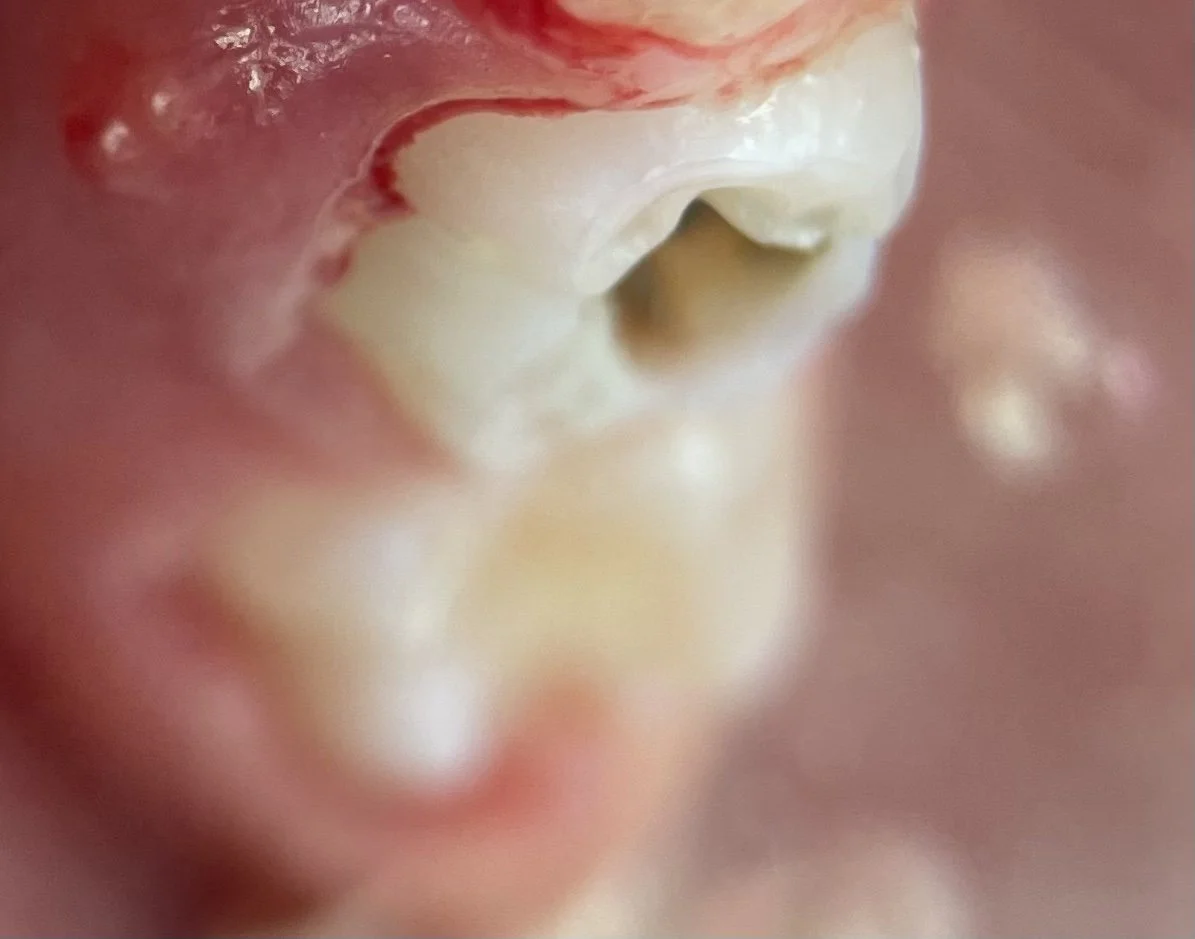

Extensive cavities have multiple noticeable darks spots, along with missing tooth structure.

An extensive cavity in a primary tooth with a gingival infection. Removal of these teeth with a space maintainer is usually recommended.